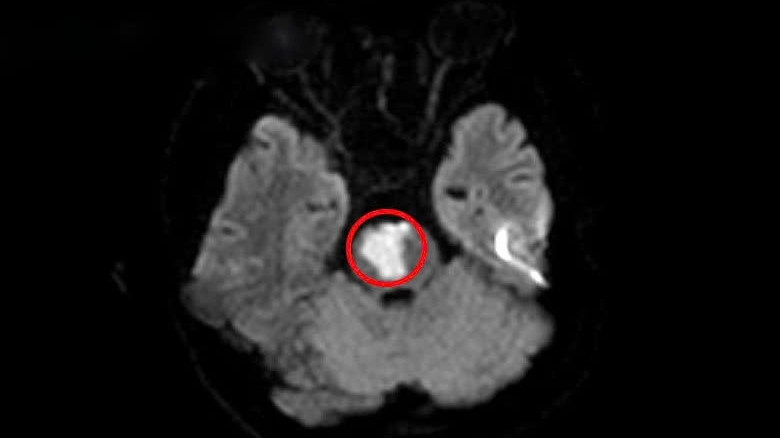

Đây là một trường hợp bệnh nhân đột quỵ vừa được Bệnh viện Nhân dân 115 (TP Hồ Chí Minh) chẩn đoán kịp thời giúp hồi phục hoàn toàn.

Theo đó, bệnh nhân có thói quen hút shisha thường xuyên và ngày càng tăng dần trong suốt một năm vừa qua.

Nhờ chẩn đoán kịp thời và điều trị đặc hiệu bằng thuốc kháng đông, người bệnh đã phục hồi hoàn toàn.

Theo thông tin chia sẻ của PGS.TS.BS Nguyễn Huy Thắng - Trưởng Khoa Bệnh lý mạch máu não Bệnh viện Nhân dân 115, huyết khối tĩnh mạch (venous thrombosis) xảy ra khi cục máu đông hình thành trong tĩnh mạch, thường ở chân hoặc có thể di chuyển đến phổi. Nếu xảy ra ở các tĩnh mạch khác, như tĩnh mạch não, nó được gọi là huyết khối tĩnh mạch não. Đây là một tình trạng nguy hiểm, có thể dẫn đến biến chứng nghiêm trọng như đột quỵ hoặc tử vong.